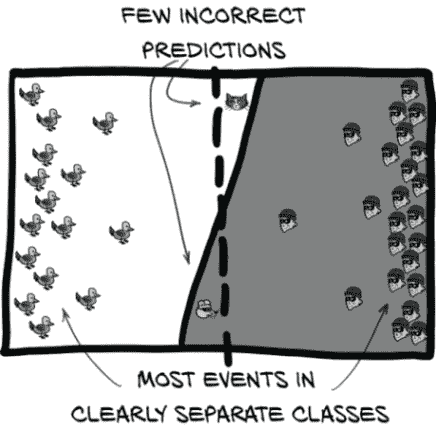

图 12.4 中的猫、鸟、啮齿动物和强盗构成了我们的四个分类象限。它们由人类标签和狗的分类阈值分隔。

在图 12.4 中,我们将使用两个阈值。第一个是人为决定的将入室盗窃犯与无害动物分开的分界线。具体来说,这是为每个训练或验证样本分配的标签。第二个是狗确定的分类阈值,它决定了狗是否会对某物吠叫。对于深度学习模型,这是在考虑样本时模型产生的预测值。

这两个阈值的组合将我们的事件分成四个象限:真/假阳性/阴性。我们将关注的事件用较深的背景色进行阴影处理(因为那些坏家伙总是在黑暗中潜行)。

当然,现实要复杂得多。并不存在一个关于入室盗窃犯的柏拉图理想,也没有一个相对于分类阈值的单一点,所有入室盗窃犯都会在那里。相反,图 12.5 向我们展示了一些入室盗窃犯会特别狡猾,一些鸟类会特别烦人。我们还将把我们的实例放在一个图中。我们的 X 轴将保持每个事件的吠声价值,由我们的一只看门狗确定。我们将让 Y 轴代表我们作为人类能够感知的一些模糊特质,但我们的狗却无法感知。

由于我们的模型产生二元分类,我们可以将预测阈值视为将单一数值输出与我们的分类阈值值进行比较。这就是为什么我们要求图 12.5 中的分类阈值线是完全垂直的。

图 12.5 每种事件都会有许多可能的实例,我们的看门狗需要评估。

每个可能的入室盗窃犯都是不同的,因此我们的看门狗将需要评估许多不同的情况,这意味着更多犯错的机会。我们可以看到明显的对角线将鸟类与入室盗窃犯分开,但普雷斯顿和洛克西只能在这里感知 X 轴:他们在我们的图中间有一组混乱、重叠的事件。他们必须选择一个垂直的吠声价值阈值,这意味着他们中的任何一个都不可能完美地做到。有时候把你的家电搬到他们的货车上的人是你雇来修理洗衣机的维修人员,有时候入室盗窃犯会开着一辆侧面写着“洗衣机维修”的货车出现。期望狗能够察觉到这些微妙之处注定会失败。

我们要使用的实际输入数据具有高维度–我们需要考虑大量 CT 体素值,以及更抽象的事物,如候选大小、在肺部的整体位置等等。我们模型的工作是将每个事件及其属性映射到这个矩形中,以便我们可以使用单一垂直线(我们的分类阈值)清晰地分离这些正面和负面事件。这是通过我们模型末端的nn.Linear层完成的。垂直线的位置与我们在第 11.6.1 节中看到的classificationThreshold_float完全对应。在那里,我们选择了硬编码值 0.5 作为我们的阈值。

请注意,实际上,所呈现的数据不是二维的;在倒数第二层之后,它变成了非常高维度,到输出时变成了一维(这里是我们的 X 轴)–每个样本只有一个标量(然后被分类阈值二分)。在这里,我们使用第二维(Y 轴)来表示我们的模型无法看到或使用的每个样本特征:例如患者的年龄或性别,结节候选在肺部的位置,甚至模型尚未利用的候选局部特征。它还为我们提供了一种方便的方式来表示非结节和结节样本之间的混淆。

图 12.5 中的象限区域和每个区域中包含的样本数将是我们用来讨论模型性能的值,因为我们可以使用这些值之间的比率来构建越来越复杂的指标,以客观地衡量我们的表现。正如他们所说,“证据在于比例。”¹ 接下来,我们将使用这些事件子集之间的比率来开始定义更好的指标。

相反,我们想看到一个类似图 12.15 的图像。在这里,我们的标签阈值几乎是垂直的。这就是我们想要的,因为这意味着标签阈值和我们的分类阈值可以相当好地对齐。同样,大多数样本集中在图表的两端。这两件事都要求我们的数据易于分离,并且我们的模型具有执行该分离的能力。我们的模型目前具有足够的容量,所以问题不在于此。相反,让我们看看我们的数据。

图 12.15 一个训练良好的模型可以清晰地分离数据,使得很容易选择一个具有少量折衷的分类阈值。